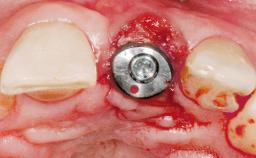

A 36-year-old female patient was referred for the replacement of the upper left central incisor (tooth 21), which had fractured. Although the tooth had been asymptomatic for many years, the crown began to loosen, at which time she presented to her dentist for an assessment. Teeth 21 and 22 had both been endodontically treated many years previously. She was a healthy individual and a non-smoker.